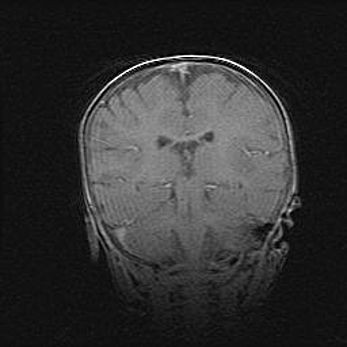

Наружная гидроцефалия с возможной атрофией височных областей.

Возраст: 28 дней

Вес: 3670 г

Пол: мужской

Окружность головы: 38 см

Срок гестации: 40 недель

Гидроцефалия головного мозга у новорожденных – это заболевание, которое характеризуется скоплением избыточного количества спинномозговой жидкости в желудочковой системе головного мозга в результате затруднения её перемещения от места выработки к месту поглощения в кровеносную систему или вследствие нарушения абсорбции. При открытой наружной форме гидроцефалии у новорожденных расширяются и переполняются субарахноидные пространства.

При нормотензивных  формах,  которые,  как  правило,  являются  следствием  перенесенных ишемических  повреждений  паренхимы  мозга,  возможно  сочетание микроцефалии  с нормотензивной гидроцефалией. В основе данных изменений лежит атрофия больших полушарий с преимущественной  локализацией  в  лобно-височных  областях.